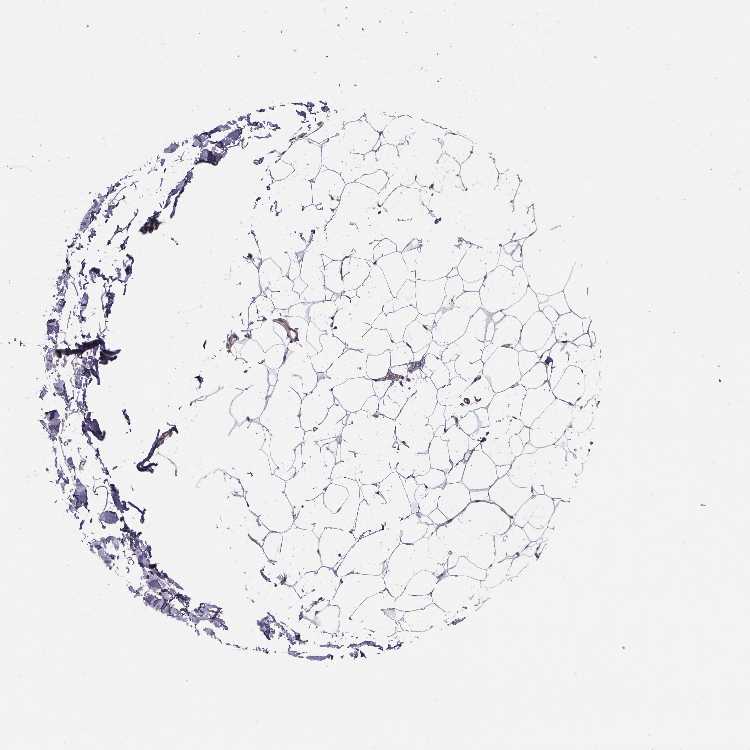

BREAST - Antibody stainingi

Antibody staining in the annotated cell types in the current human tissue is reported as not detected, low, medium, or high, based on conventional immunohistochemistry profiling in selected tissues. This score is based on the combination of the staining intensity and fraction of stained cells.

Each image is clickable and will lead to virtual microscopy that enables deeper exploration of all samples and also displays staining intensity scores, fraction scores and subcellular localization as well as patient and tissue information for each sample.

Antibody HPA055312Antibody CAB047343Antibody CAB069914

Adipocytes Not detectedNot detectedLow

Glandular cells High-Low

Myoepithelial cells Medium-Low